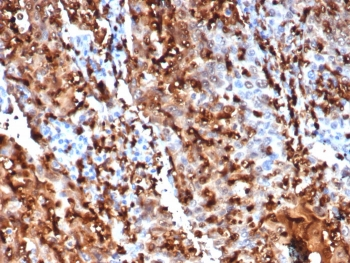

Cathepsin D Antibody

| Catalog Number | orb621663 |

|---|---|

| Category | Antibodies |

| Description | Cathepsin D Antibody |

| Species/Host | Rabbit |

| Clonality | Recombinant |

| Tested applications | FC, ICC, IHC, IP, WB |

| Reactivity | Human, Mouse |

| Antibody Type | Primary Antibody |

| Conjugation | Unconjugated |

| UniProt ID | P07339 |